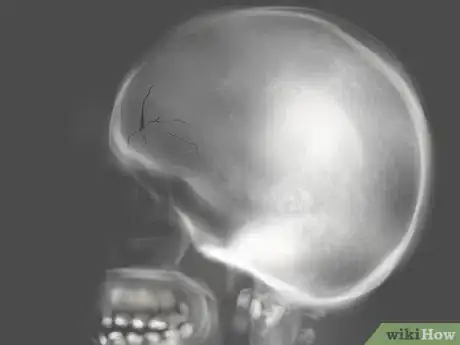

2Osserva la presenza di ossa rotte o fratturate. Se hai ricevuto un colpo forte sul viso, assicurati di non avere eventuali rotture o fratture sotto la pelle. Questo è particolarmente importante qualora il taglio fosse dovuto a un incidente automobilistico o una percossa violenta [8] .